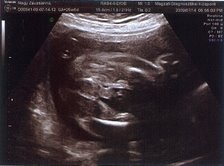

Nézzétek a kukim:

Mindjárt megpróbálom felnagyítani:

én csak közelről ismerem fel az ilyet :lol: jó,hogy felnagyítottad :lol:

Milyen édes kis arcocskája van :)

Édes kis turcsi orra lesz, mint apukájának van.... anyum szerint tiszta apja :lol: :lol: :lol: :lol: :lol: :lol: :lol: :lol:

Jajj de szép Benőke! :) És tényleg látszik a kis kukija. :) Jajj meg azok a csöpp kis lábacskák! :) Na és a kis pofija... :) Megvallom könny szökik a szemembe... Hogy mennyire várom már, hogy láthassam a teljes valójában! :) GOndolom te még jobban.:)

Leírhatatlan érzés volt látni ilyen formában is. Anyum szerint már most tiszta apja a gyerek :lol: :lol: :lol: :lol: :lol: :lol: :lol: :lol:

Hát igen, apja méreteire hajaz a drágám úgy látszik :shock: :shock: :shock: :shock: :shock: :shock:

A doki ott mosolygott végig. De marhára nem tetszett, amikor beszólt nekem, hogy eléggé vaskos a hasfalam :evil: :evil: :evil: :evil: :evil: :evil: Én is majdnem mondtam neki valamit... de hát anyu előtt csak nem :? :? :? :? :? :?

Végleges név még mindig nincs.